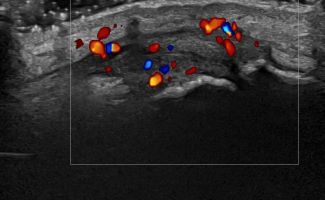

Hand Ultrasound examines joints, tendons, ligaments, nerves, and soft tissues of the hand. Pathologies that can be diagnosed by Hand Ultrasound are numerous, including:

Rheumatic Diseases

- Rheumatoid Arthritis

- Psoriatic Arthritis

Dynamic Testing: Hand Ultrasound allows assessment of hand movement dynamically. This is particularly important for evaluating conditions affecting the range of movement, such as tendonitis and joint injuries.